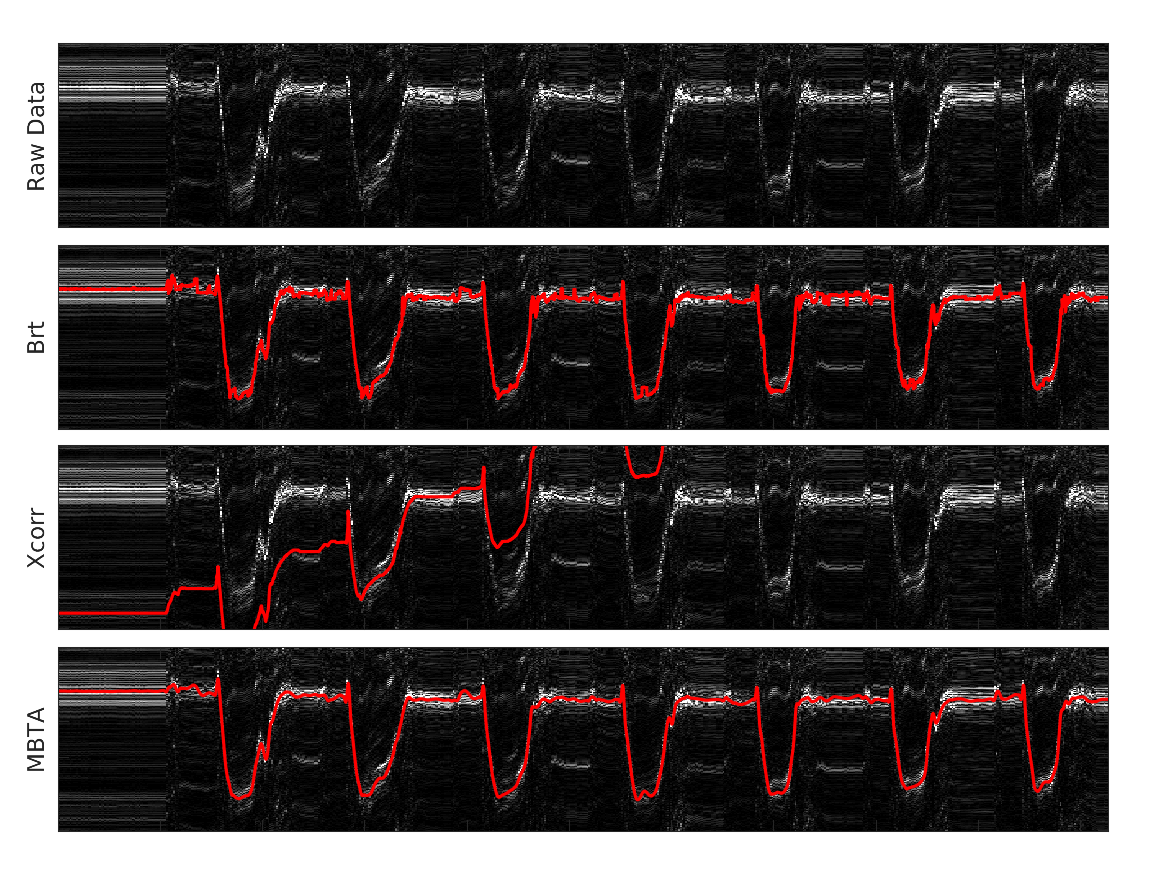

1. A模式超声技术

A模式超声技术是一种通过测量超声波在组织中传播的速度和时间来评估组织特性的方法。在本研究中,我们采用单元件超声换能器,通过连续发送超声波并接收反射信号,实时跟踪肌肉厚度的变化。

4. 动态现实任务实验

在验证了模型在受控条件下的准确性后,我们进一步将其应用于动态现实任务中,包括举重、骑自行车、跑步机运动和室外运动。通过佩戴可穿戴A模式超声设备,实时记录肌肉厚度变化,并估计关节扭矩。

2. 动态现实任务实验结果

在动态现实任务中,可穿戴A模式超声设备成功地实时记录了肌肉厚度变化,并估计了关节扭矩。尽管动态活动中的肌肉活动模式更为复杂,但我们的方法仍然能够在举重、骑自行车、跑步机运动和室外运动等任务中提供可靠的关节扭矩估计。